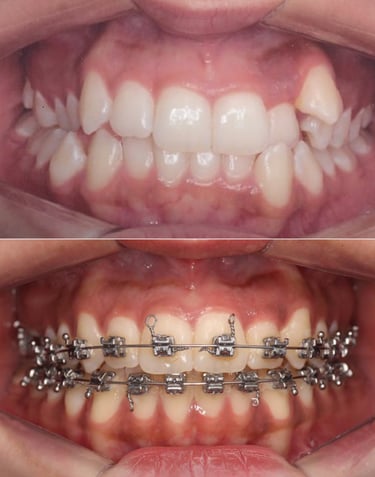

EVOLUÇÃO